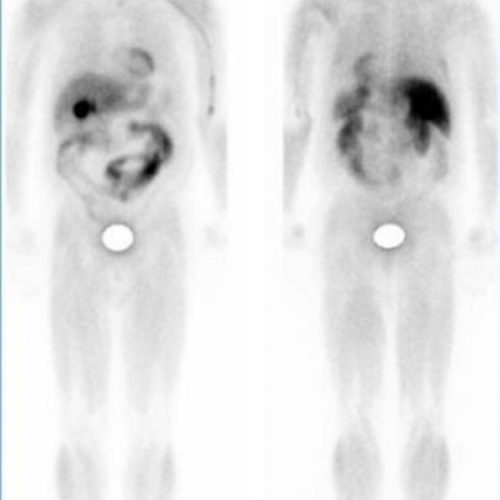

GAMMAGRAFÍA DE RECEPTORES DE LA SOMATOSTATINA, OCTREOSCAN

Estudio y extensión de tumores con receptores para la somatostatina.